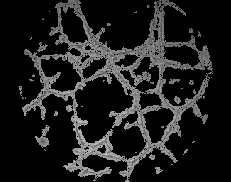

De cada una de las imágenes (ver Fig.3) se pueden extraer una serie de parámetros consensuados como significativos en los procesos angiogénicos. En todas las imágenes se puede observar la presencia de canales (cerrados y abiertos) de diferentes longitudes y con su característica intrínseca de linealidad, células aisladas, grumos de células, fondo de textura uniforme y un halo circundante de mayor brillo que es una interferencia incorporada por condiciones de contorno en la adquisición. El procesamiento individual se puede dividir a su vez en 3 partes: 1) pre-procesamiento, 2) realce de las morfologías de interés, y 3) post-procesamiento.

El siguiente procedimiento es aplicar un proceso de binarización (ver Fig.11), seguido de otro de esqueletonización (ver Fig.12), de forma que quedan perfectamente delineados los canales detectados. En la figura 13 se puede observar la superposición de la imagen resultantes del pre-procesamiento (paso 1) y del procesamiento (paso 2); se marcan en negro los canales conectados y en blanco los canales aislados (no conectados).

Figura 11. Binarización Figura 12. Esqueletonización

Figura 13. Superposición de imagen con trazado de canales detectados.